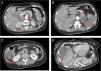

Computed tomography angiography (CTA) of the abdomen/pelvis (Figure 2A, 2B and 2C) at patient admission: complete splenic infarction without contrast enhancement except for a fine capsule; splenic artery occlusion. Hypodense ill-defined lesion in the pancreas tail measuring 55×38 mm with adjacent fat densification, but without contrast enhancement leading to a differential diagnosis between ischemic infarct and malignant neoplasm. Heterogeneous contrast enhancement of both kidneys, with triangular parenchymal areas of lower attenuation, suggestive of ischemic renal foci. Heterogeneous hepatomegaly with areas of non-contrast enhancement, the biggest one in segments VII and VIII; a similar area on the liver border and smaller hypodense areas that, in this context, could represent occlusive arterial conditions. Small parietal thrombus (9mm) in the left lateral aortic wall, in the axial plane of the celiac trunk, with no evident atheromatous lesions.

Figure 2.CT scan of the abdomen/pelvis showing total hypodensity of the spleen representing a complete infarct, without contrast enhancement except for a fine capsule. Splenic artery occlusion. Hypodense ill-defined lesion in the pancreas tail, measuring 55×38 mm with adjacent fat densification, but without contrast enhancement leading to a differential diagnosis between ischemic infarct and malignant neoplasm. Heterogeneous contrast enhancement of both kidneys, with triangular parenchymal areas of lower attenuation, suggestive of ischemic renal foci. Heterogeneous hepatomegaly with areas of non-contrast enhancement, the biggest one in segments VII and VIII; similar area on the liver border and smaller hypodense areas that, in this context, can represent occlusive arterial conditions. Small parietal thrombus (9mm) in the left lateral aortic wall, in the axial plane of the celiac trunk, with no evident atheromatous lesions.

Although there were no clinical signs of acute abdomen, the pain in the upper quadrants could not be ignored. Moreover, blood test results (leukocytosis, elevated CRP and liver enzymes) were excessively abnormal, which could be explained only by the acute foot ischemia. Vascular events in the abdominal cavity, an infectious process (although there was no fever), neoplasm and pancreatitis had to be sought out. The CTA of the abdomen/pelvis showed an aortic wall thrombus in the axial plane of the celiac trunk and a complete splenic artery occlusion (Figure 2A and 2B). Multiple infarcts were present in some subsidiary arterial territories of the abdominal aorta: complete splenic infarct, renal ischemic foci, hepatic infarcts in distinct segments and a hypodense area in the pancreas tail leading to a differential diagnosis between pancreatic infarct and malignant neoplasm (Figure 2B, 2C and 2D). MRI of the abdomen/pelvis showed that the pancreatic lesion was an ischemic lesion and not a tumor (Figure 3A and 3B).